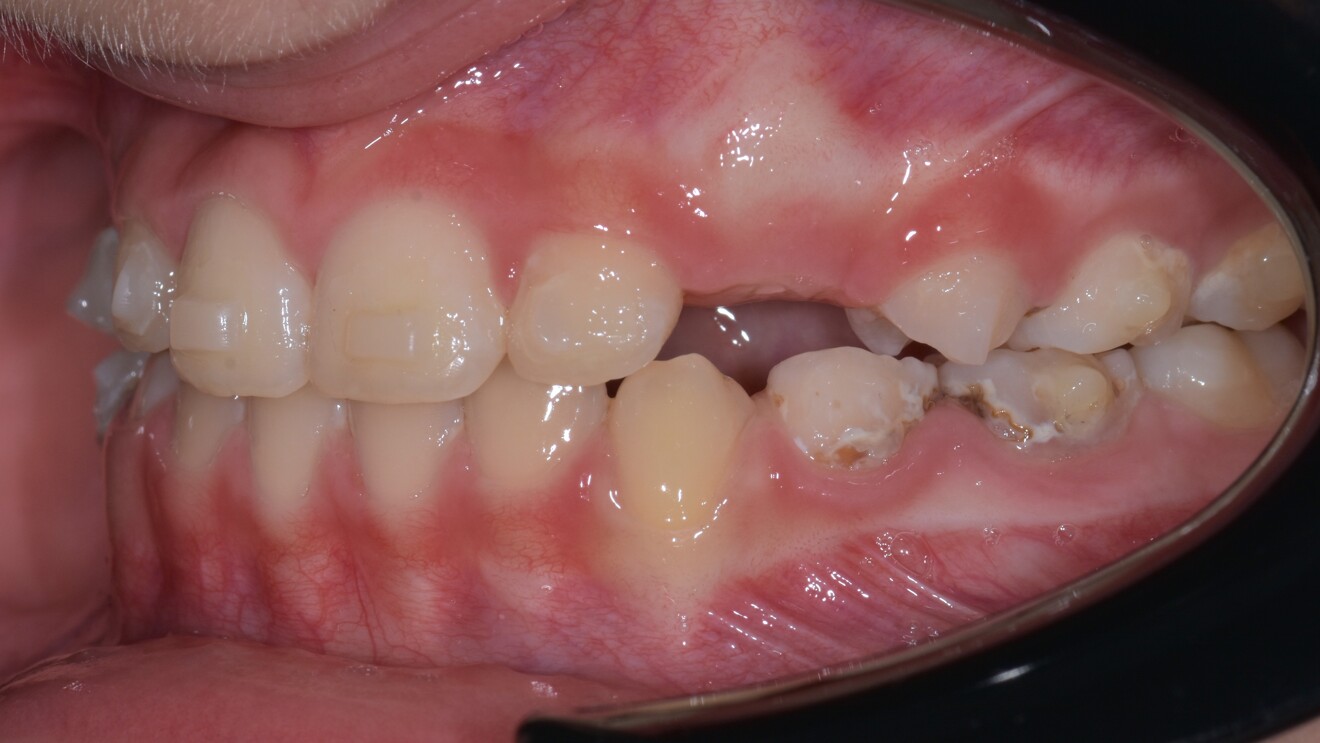

Figs. 1d–h: Pre-treatment records. Intra-oral photographs.